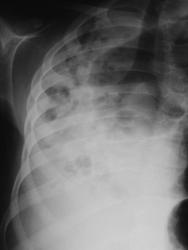

Во всей видимости речь идет о врожденной патологии, которую Воль-Эбштейн "обзывает" гипоплазиями, агенезиями и аплазиями. Речь идет о выраженной гипоплазии правого легкого, возможно об агенезии правого главного бронха. Компенсаторное расширение левого лёгкого свидетельствует о том, что оно заполняет "свободную нишу". Раньше для подтверждения данной патологии проводили обязательно бронхографию, мы-же, теперь довольно хорошо выявляем это линейной томографией, как в прямой, так и в боковой проекциях.

Ну а раз операций не было, то предположу гипоплазию верхнедолевого бронха с аплазией на уровне промежуточного и аплазией легкого, с отсутствием функционально состоятельной легочной ткани.

Валентин Львович; как говорят французы: снимаю шляпу! Я выставил диагноз: Right Pulmonary Hypoplasia; Pleural effusion; empyema is suggested. CT scan is recommended. Т.к. я не особо силён в описании на русском языке; воспользуюсь плагиатом! Один мой очень хороший друг радиолог из Украины, описал эти снимки примерно так: Правый гемиторакс полностью затенен с включениями воздуха, соединяющимимся местами между собой. Все средостение находится справа, трахея и главные бронхи хорошо видны, не сужены. Викарная эмфизема слева; сформировавщаяся годами. Диафрагма и синусы справа не видны, но вероятно диафрагма расположена занчительно выше обычного. В данном случае затемнение не гомогенное при смещенном средостении в пораженную сторону: диф. диагноз: а) абсцедирующая пневмония с объемным уменьшением; б) кистозная гипоплазия всего легкого. У ребенка второй вариант - врожденная патология правого легкого с его недоразвитием, объемным уменьшением и множественными кистозными (мешотчатыми) бронхоэктазами, которые мы и видим, как просветления. С учетом отсутствия видимости синусов - все это осложнилось обострением хронического воспалительного процесса + плевритом.